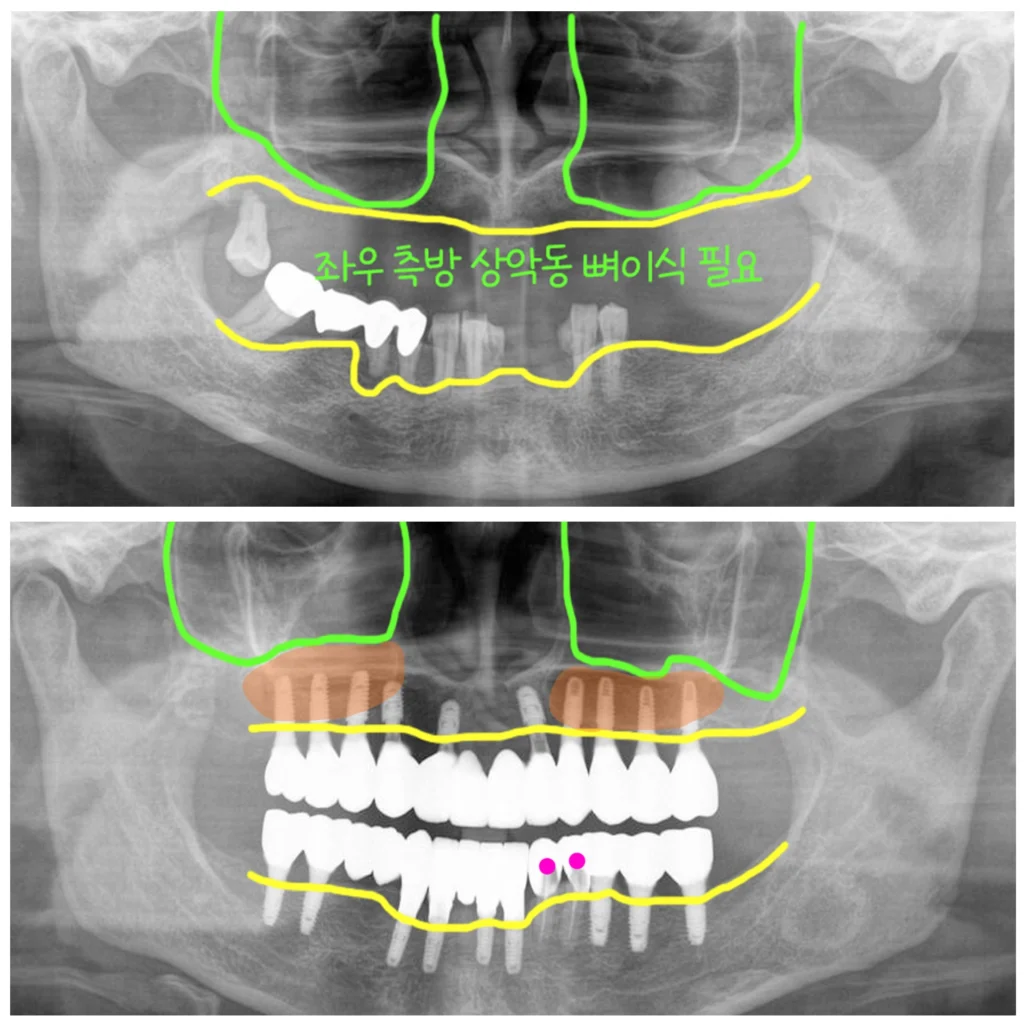

위턱에는 제일 뒤에 어금니 한 개만 남아있는 무치악 상태였습니다. 엑스레이에서 보시듯이 상악동이 앞뒤로 아주 길면서 크고 가용골(이용할 수 있는 뼈)이 전혀 없어서 뼈이식과 함께 임플란트를 식립해서 고정을 얻기가 어려운 상태였습니다.

첫번째 수술입니다. 상악에 한개 남은 치아는 제거하고 대량의 뼈이식을 진행했습니다. 고정을 얻을 만한 뼈가 없어서 임플란트 식립은 뼈이식 후 6개월 차에 진행하기로 했습니다.

그래서 위쪽은 즉시하중을 적용하지 못하고 미리 만들어 둔 임시틀니를 착용했습니다.

하악은 발치와 동시에 임플란트를 9개 식립했고, 2개의 치아는 예방적 신경치료를 한 후 크라운 프랩을 하고 아래 전체를 묶어서 수술당일 임시치아를 적용했습니다.